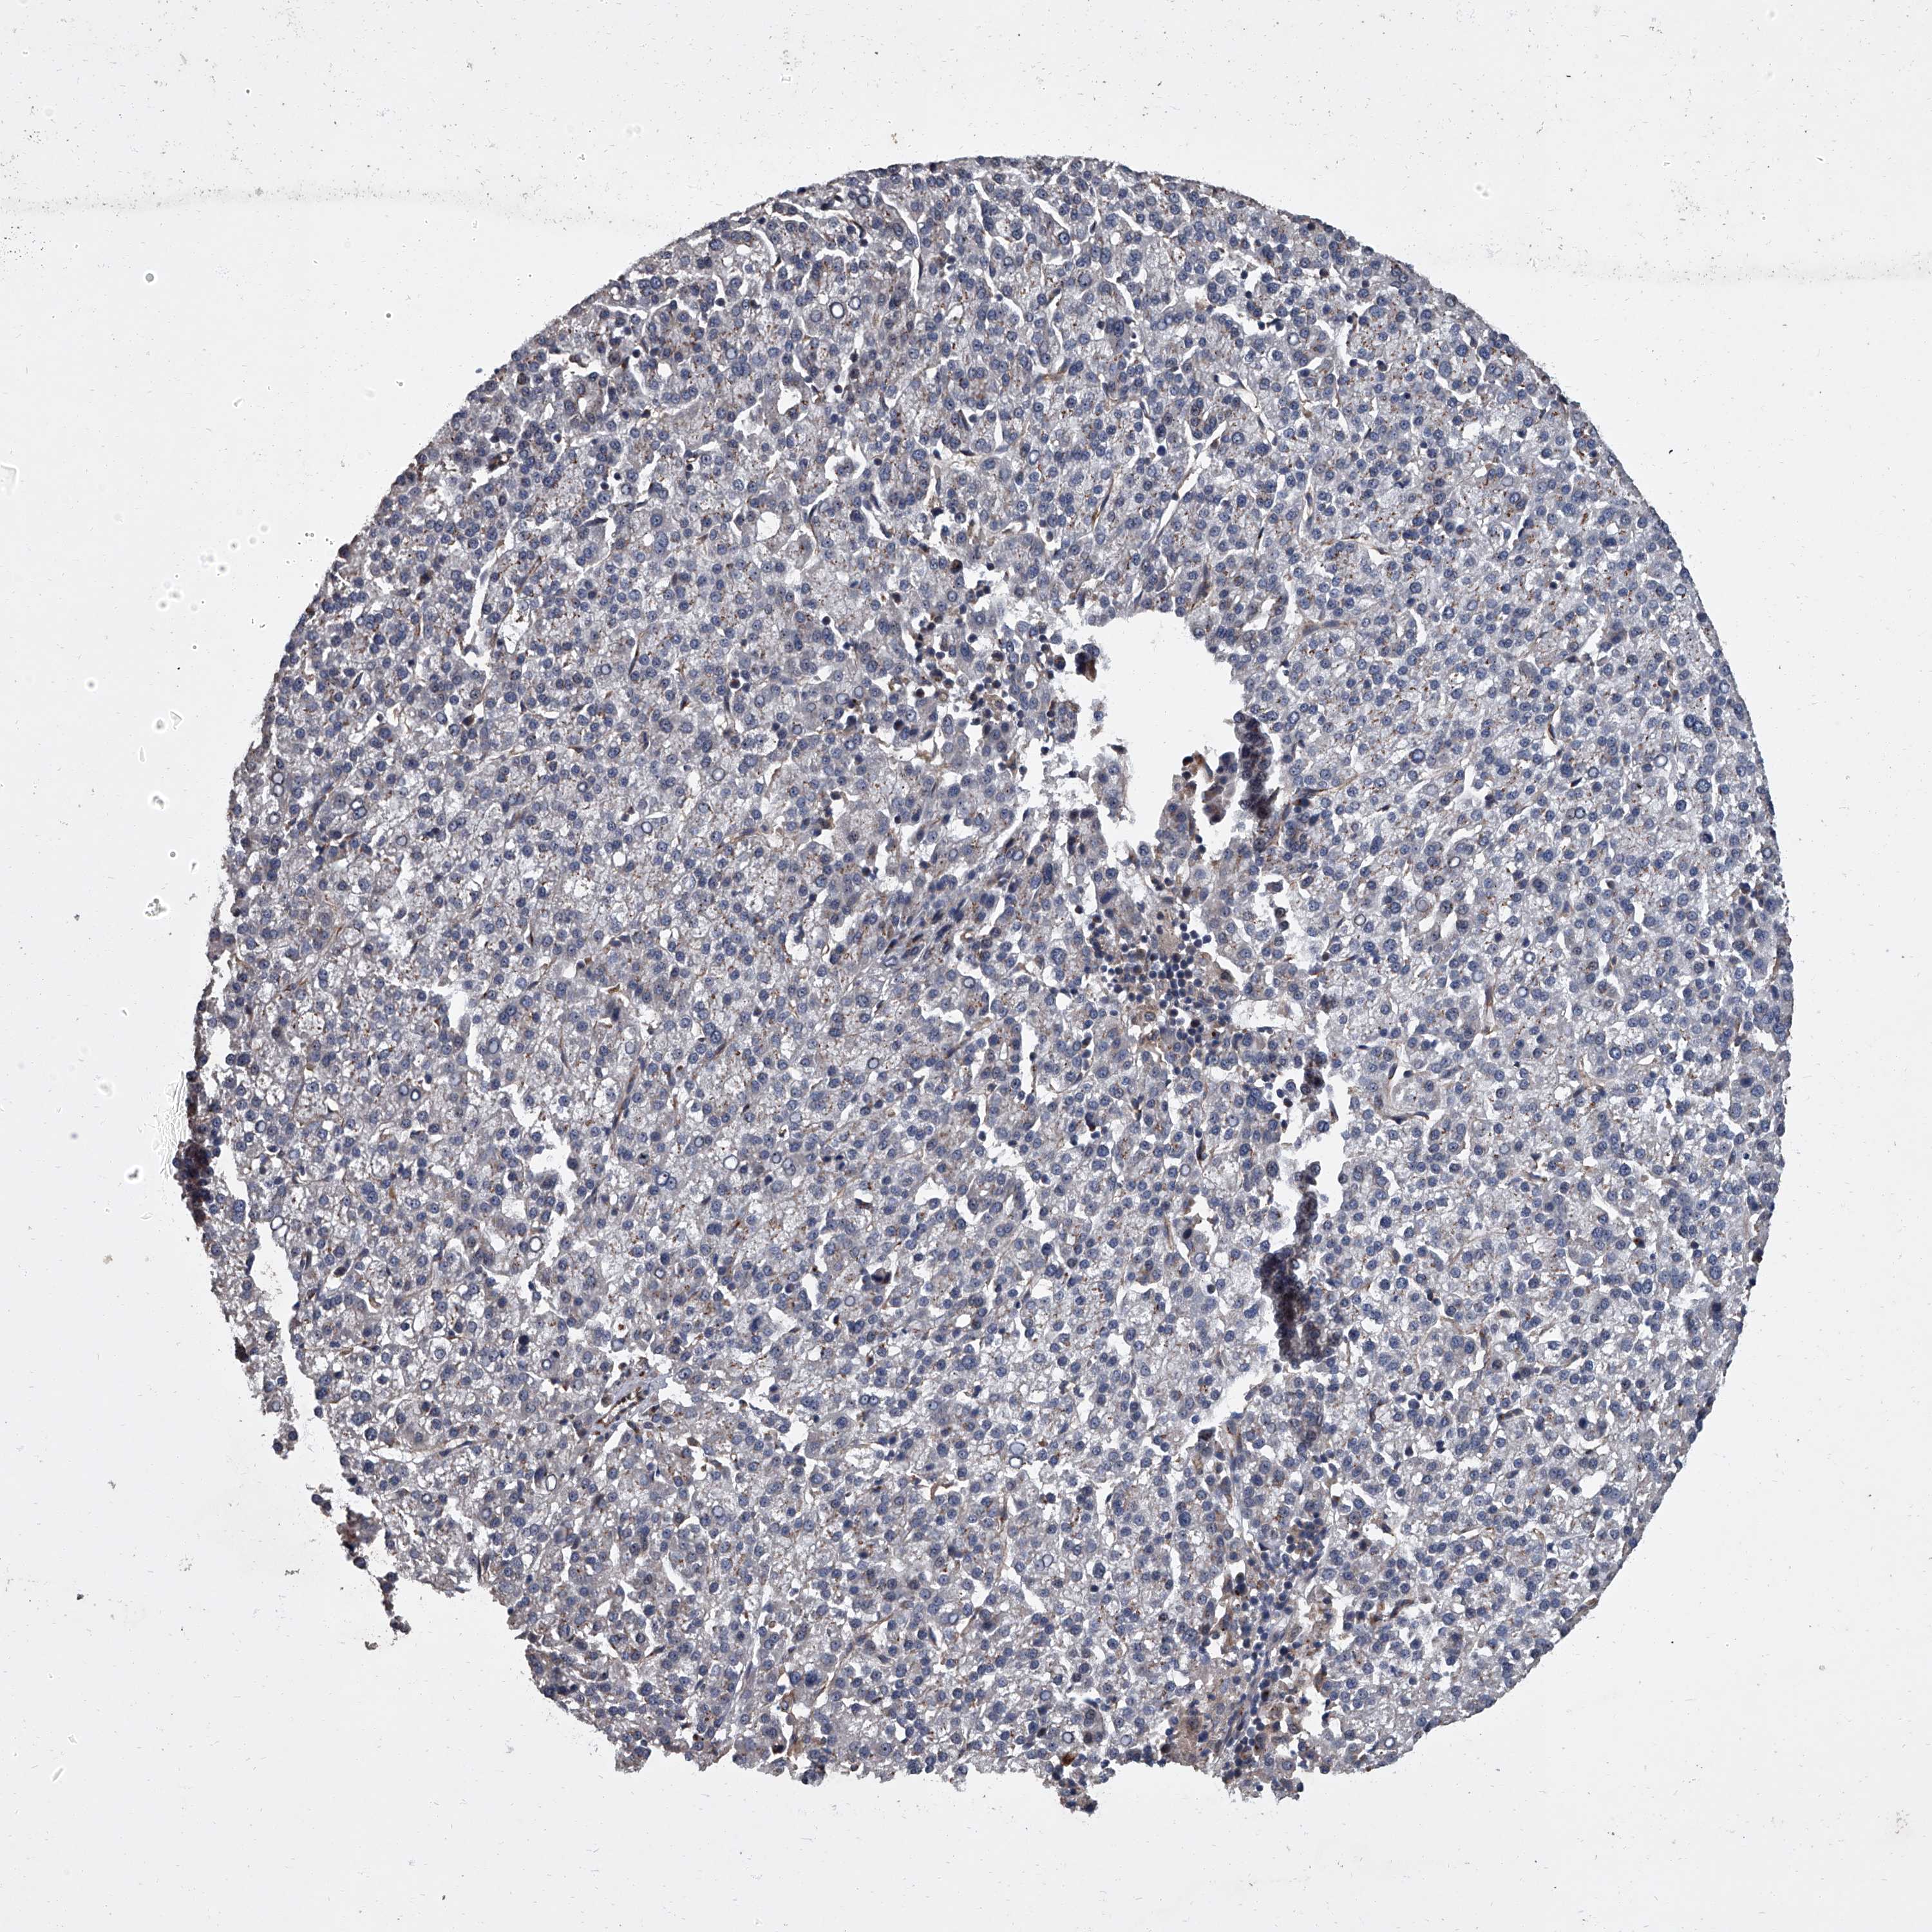

LIVER CANCER - Protein expressioni

A mouse-over function shows sample information and annotation data. Click on an image to view it in a full screen mode. Samples can be filtered based on level of antibody staining by selecting one or several of the following categories: high, medium, low and not detected. The assay and annotation is described here.

Antibody stainingi

Antibody staining in the annotated cell types in the current human tissue is reported as not detected, low, medium, or high, based on conventional immunohistochemistry profiling in selected tissues. This score is based on the combination of the staining intensity and fraction of stained cells.

Each image is clickable and will lead to virtual microscopy that enables deeper exploration of all samples and also displays staining intensity scores, fraction scores and subcellular localization as well as patient and tissue information for each sample.

Antibody HPA029347

Staining

High

Medium

Low

Not detected

Cholangiocarcinoma

Carcinoma, Hepatocellular, NOS